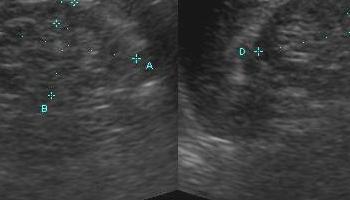

USG układu moczowego i prostaty

Jest to podstawowe badanie obrazowo-diagnostyczne w każdym podejrzeniu choroby nerek, pęcherza moczowego i prostaty. Jest elementem badania jamy brzusznej, lecz może być zlecone przez lekarza urologa jako oddzielne badanie. Obejmuje ocenę nerek, dróg moczowych, pęcherza moczowego oraz prostaty u mężczyzn. Jest badaniem podstawowym w rozpoznawaniu kamicy nerkowej, zastoju w nerkach, chorób rozrostowych nerek i pęcherza moczowego, kamicy w moczowodzie czy pęcherzu moczowym. Podczas tego badania ocenie podlega również wielkość gruczołu krokowego.

Część zdjęć pochodzi ze strony www.ultrasound-images.com